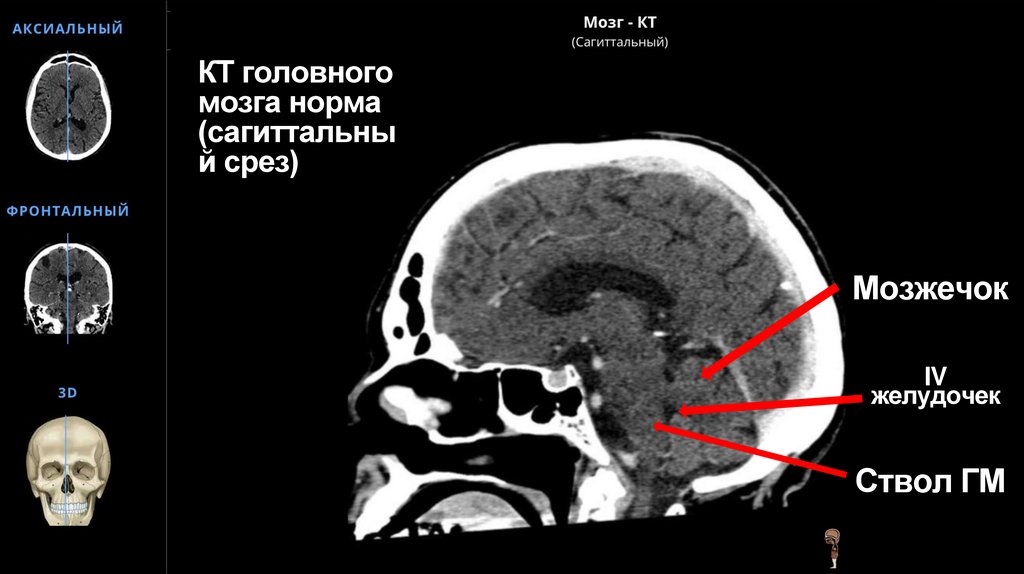

КТ головного мозга норма (сагиттальный срез)

58. КТ головного мозга норма (сагиттальный срез)

КТ головного

мозга норма

(сагиттальны

й срез)

Мозжечок

IV

желудочек

Ствол ГМ